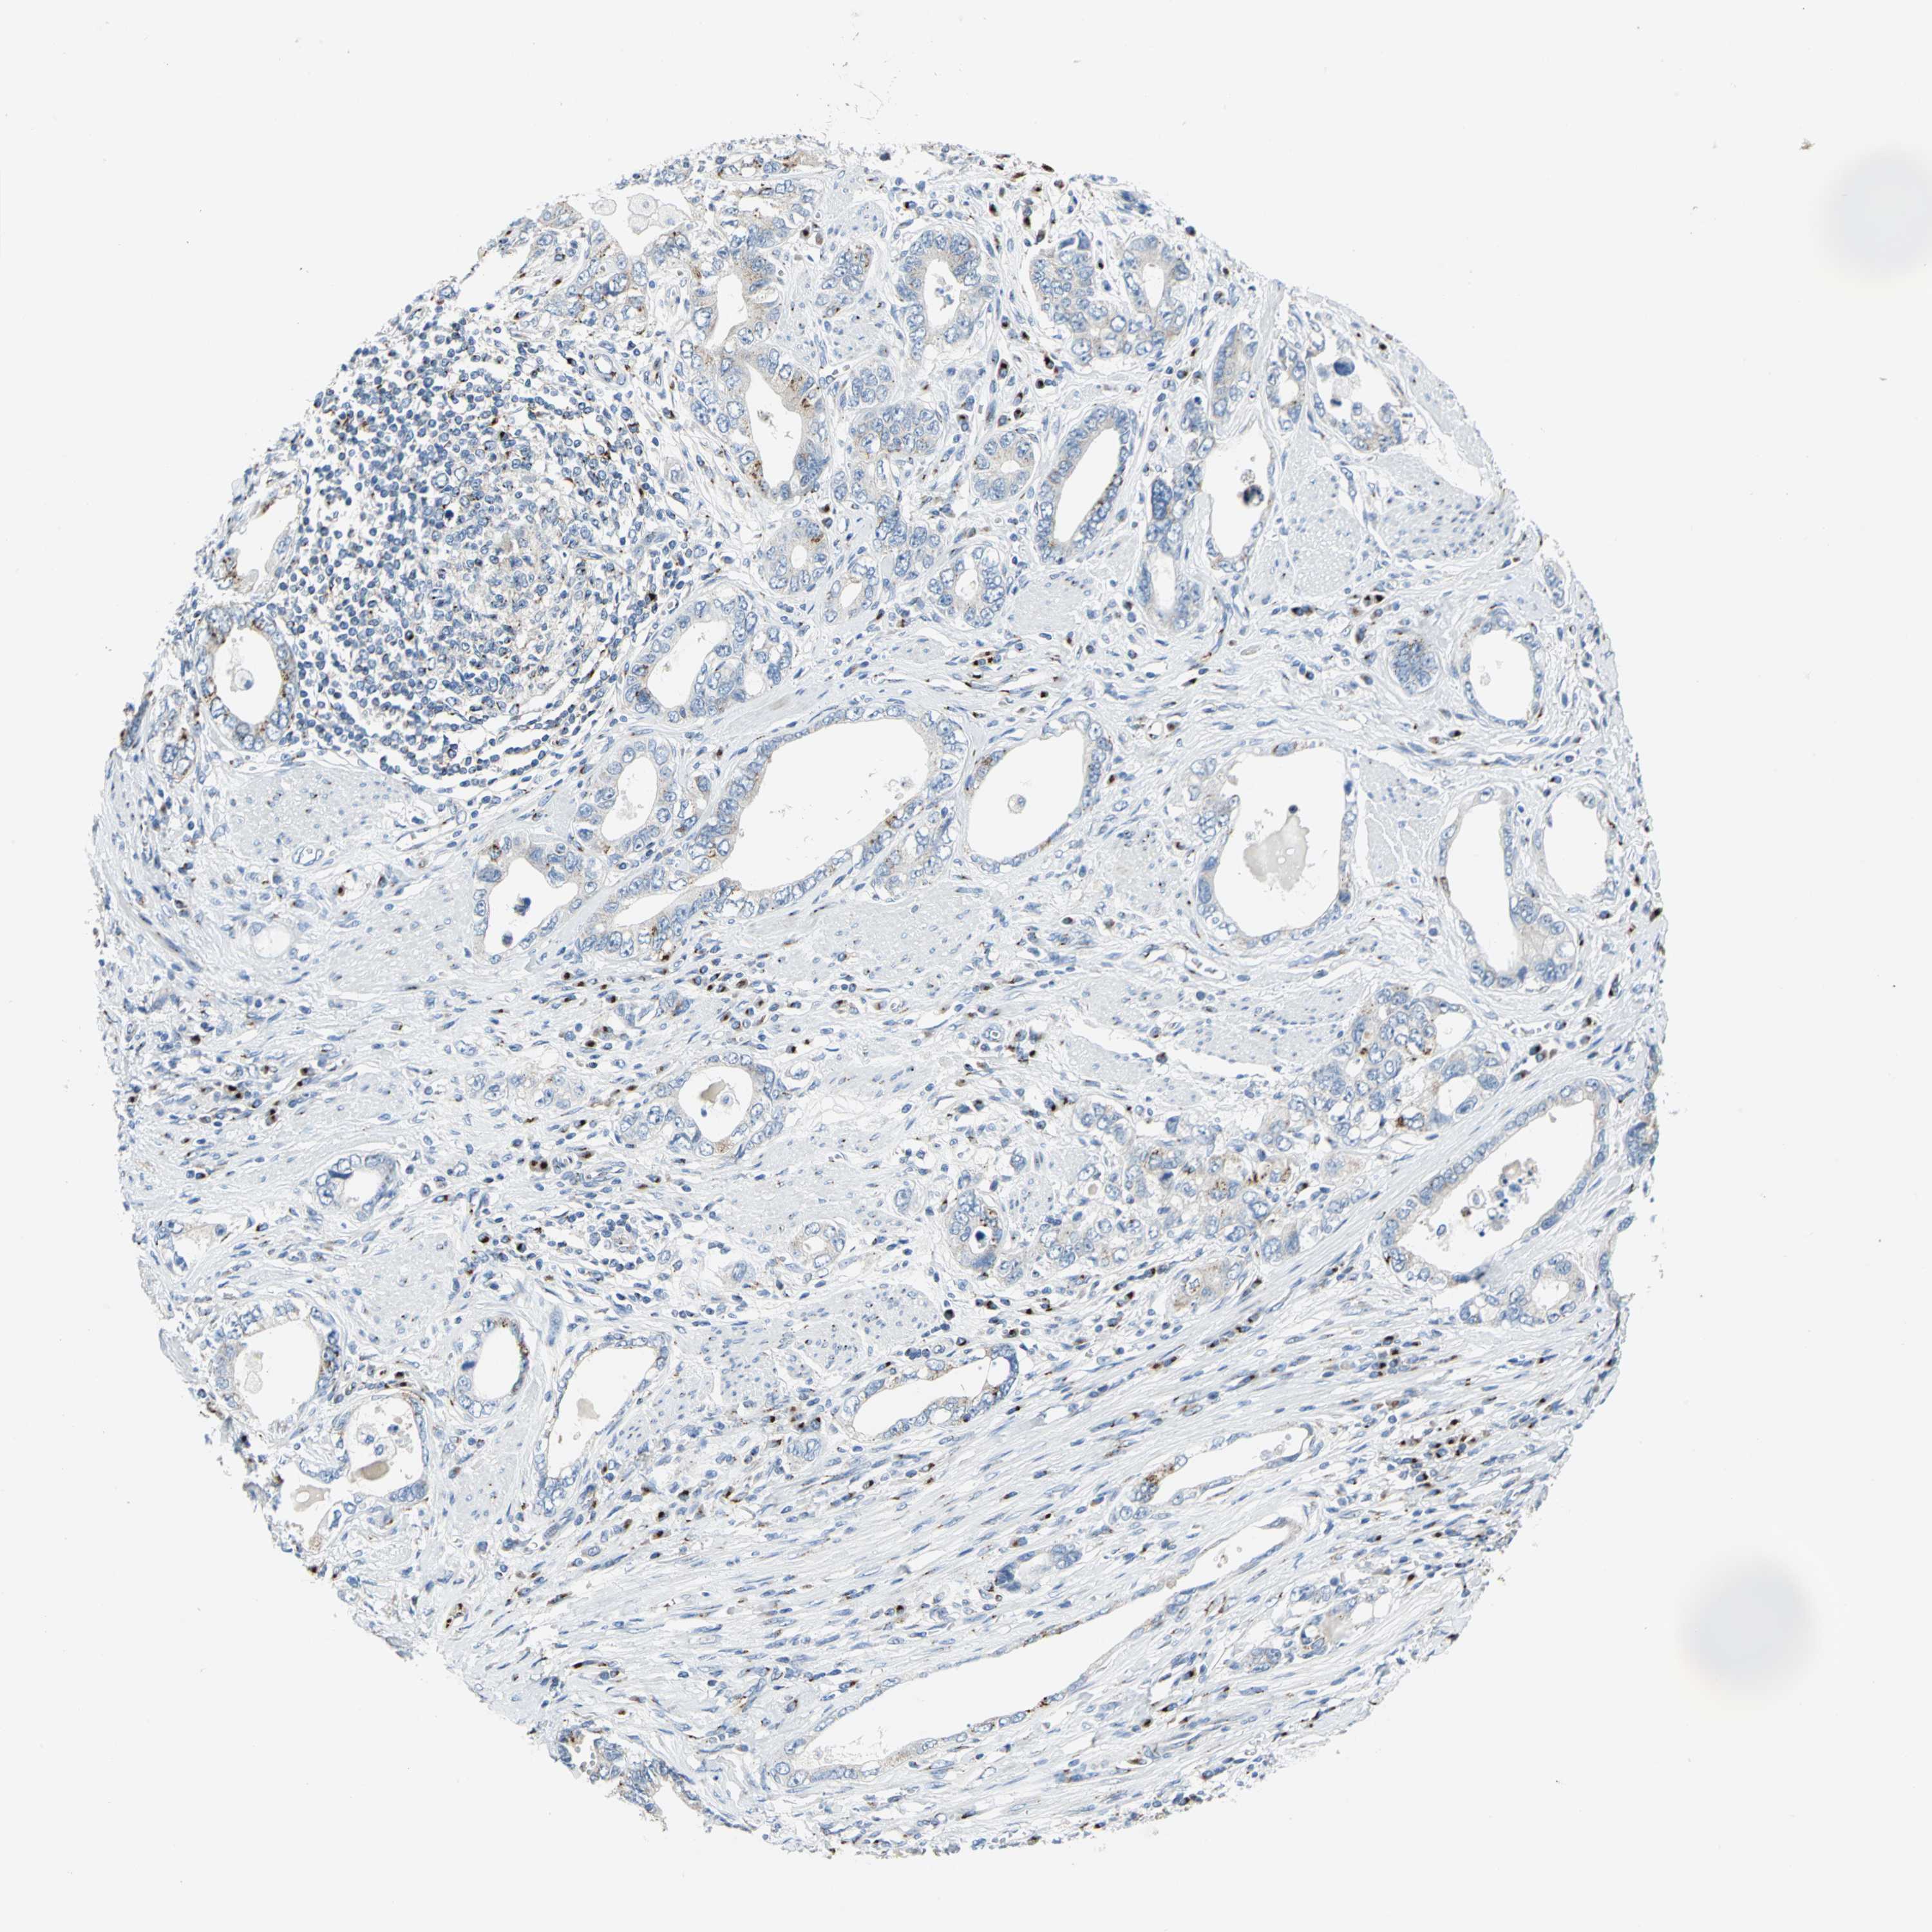

STOMACH CANCER - Protein expressioni

A mouse-over function shows sample information and annotation data. Click on an image to view it in a full screen mode. Samples can be filtered based on level of antibody staining by selecting one or several of the following categories: high, medium, low and not detected. The assay and annotation is described here.

Note that samples used for immunohistochemistry by the Human Protein Atlas do not correspond to samples in the TCGA dataset.

Antibody stainingi

Antibody staining in the annotated cell types in the current human tissue is reported as not detected, low, medium, or high, based on conventional immunohistochemistry profiling in selected tissues. This score is based on the combination of the staining intensity and fraction of stained cells.

Each image is clickable and will lead to virtual microscopy that enables deeper exploration of all samples and also displays staining intensity scores, fraction scores and subcellular localization as well as patient and tissue information for each sample.

Antibody CAB006254

Staining

High

Medium

Low

Not detected

Intensity

Strong

Moderate

Weak

Negative

Quantity

>75%

75%-25%

<25%

None

Location

Nuclear

Cytoplasmic/membranous

Cytoplasmic/membranous,nuclear

Adenocarcinoma, NOS

Adenocarcinoma, High grade